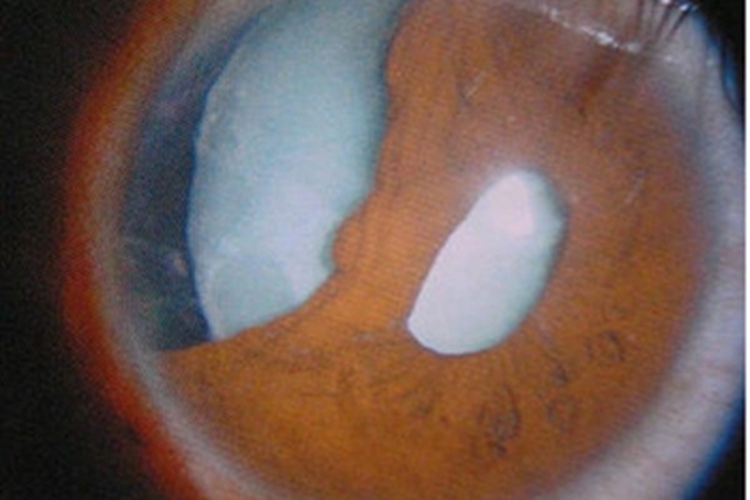

眼部钝挫伤所致白内障表现为瞳孔缘部虹膜色素上皮破裂脱落,附贴在晶状体前表面,相应的囊膜下出现混浊,可在数日后消失,或长期存在。当晶状体受到钝挫伤后,其纤维和缝合的结构受到破坏,液体向着晶状体缝合间和板层流动,形成放射状混浊,可在伤后数小时或数周内发生,可被吸收或永久存在。

眼部钝挫伤所致白内障导致的晶状体局限混浊,对视力影响不大时,以随诊观察为主。当晶状体混浊明显而影响视力时,应当施行白内障摘除术。当晶状体破裂,皮质突入前房时,可遵医嘱用糖皮质激素、非甾体抗炎药及降眼压药物治疗,待前节炎症反应消退后,再行手术摘除白内障。